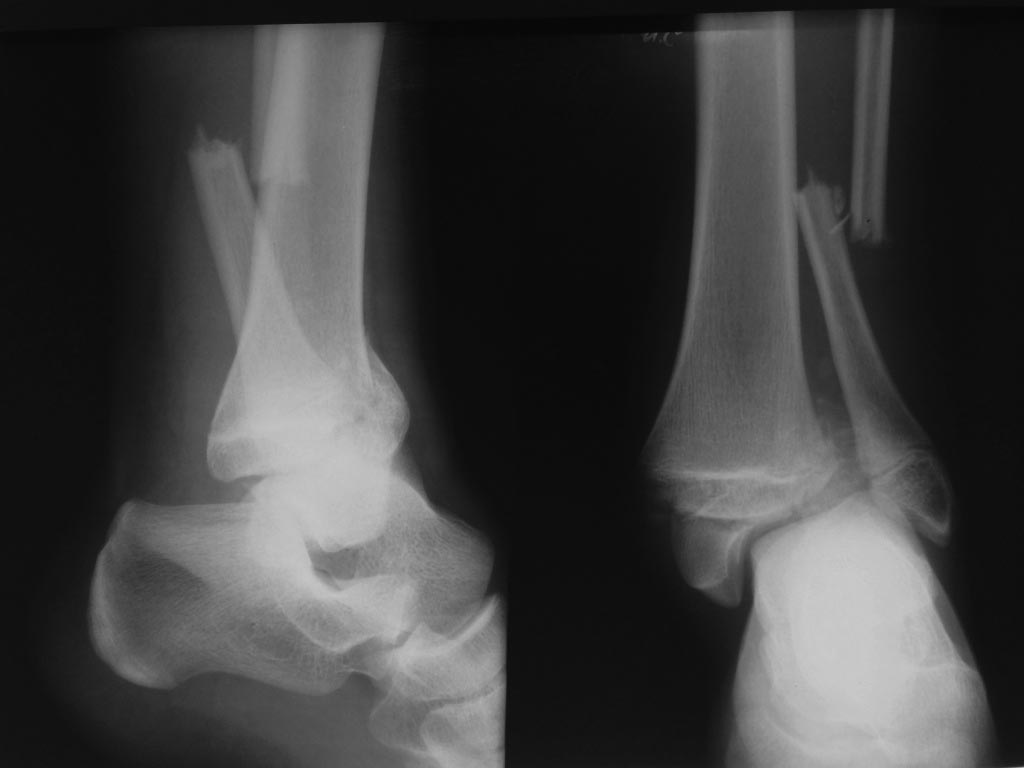

Ребенок 15 лет. Госпитализирован 25.10.14. Репозиция, затем гипс,

Имя     : 1 при поступлении.JPG

Тип     : image/jpeg

Размер  : 44771 байтов